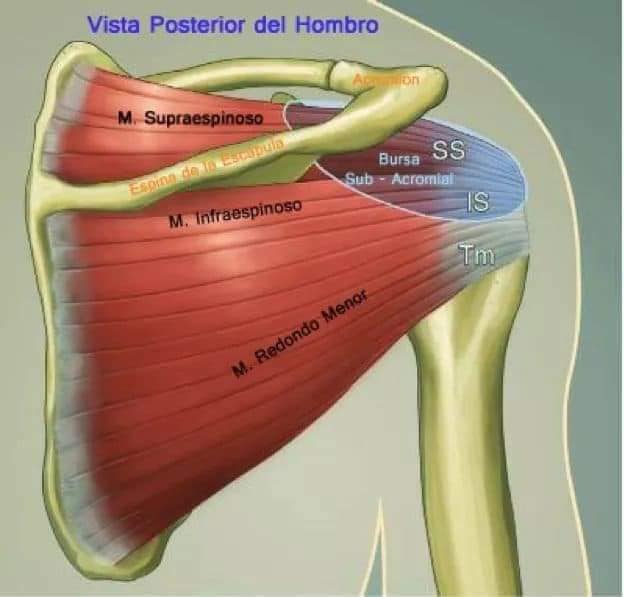

Спинні м'язи

Спинні м'язи виконують функції підтримки хребта, а також дозволяють здійснювати рухи тулуба.

Поверхневі спинні м'язи

М'язи, що піднімають лопатку: Трапецієподібний м'яз: великий м'яз, що покриває верхню частину спини. Його функція - підтримка і рух лопаток, а також забезпечення стабільності хребта.

М'язи, що ведуть лопатку до хребта: Широкий м'яз спини: великий м'яз, що розташований в нижній частині спини. Він відповідає за рухи плечей і лопаток, а також за розширення верхньої частини тулуба.